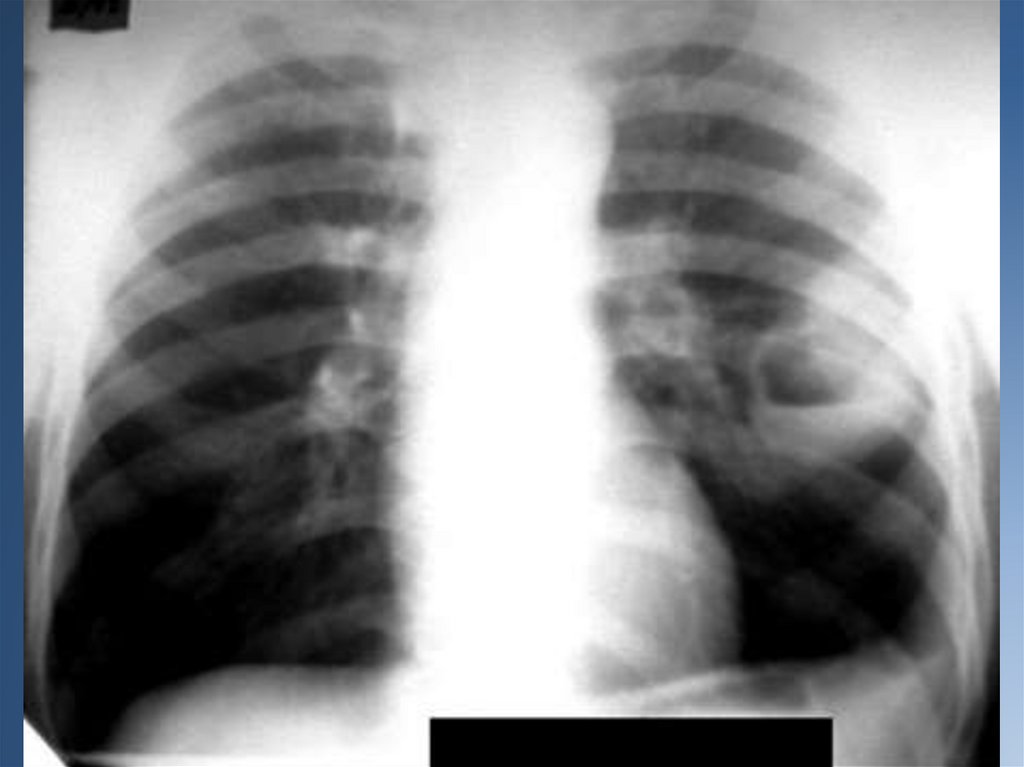

Диагностика: рентгенологический метод исследования (прямой и боковой);

исследование мокроты с нахождением в ней атипичных клеток, также

исследуется бронхиальный секрет и плевральный экссудат; компьютерная

томография; бронхоскопия (проводится забор пораженной ткани для

гистологического исследования; бронхография.